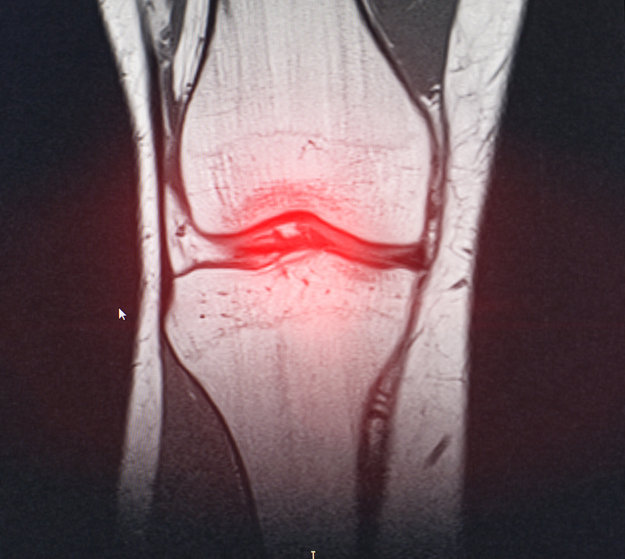

무릎에서 ‘쿠션’ 역할을 하는 반월상연골을 일부 절제하는 ‘부분 반월상 연골 절제술’이, 기대와 달리 통증이나 기능을 개선하지 못할 뿐 아니라 오히려 상태를 악화시킬 수 있다는 장기 연구 결과가 나왔다. 특히 중년층에서 흔한 ‘퇴행성 반월상연골 파열’에서는 수술 효과가 거의 없는 것으로 나타났다. 이에 치료 접근에 변화가 필요하다는 지적이 나온다.손상된 반월상연골을 일부 절제해 매끄럽게 만드는 이 수술은 전 세계적으로 널리 시행되는 대표적인 정형외과 수술 중 하나다. 특히 운동선수들에서 매우 흔하다. 핀란드 연구진이 수행한 ‘퇴행성 반월상연골 병변 연구’에서는 35~65세 환자 146명을 대상으로 부분 반월상연골 절제술의 효과를 평가했다. 약 3분의 1은 스포츠 중 부상이나 무릎 비틀림으로, 나머지 3분의 2는 퇴행성으로 손상됐다. 이 연구는 실제 수술을 받은 환자군과, 피부만 절개하고 손상 부위는 건드리지 않은 ‘위약 수술(sham surgery)’군을 무작위로 나눠 10